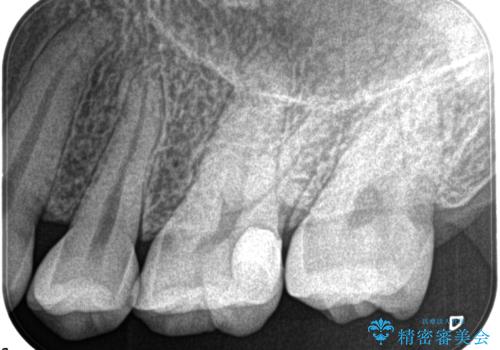

- 奥歯がズキズキ痛いことを主訴に来院されました。

検査の結果、診断を症候性不可逆性歯髄炎、症候性根尖性歯周炎とし抜髄を行っております。